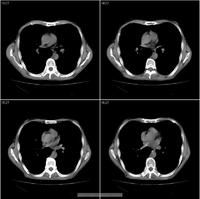

內鏡檢查:常見潰瘍位於吻合口小腸側,多數為單個潰瘍,伴黏膜糜爛 充血、水腫,活檢可除外惡性潰瘍。

胃泌酸試驗:顯示BAO增高,經五肽胃泌素或增大組織胺法,MAO明顯升高。血清胃泌素測定可增高。X線鋇餐檢查約半數病例可見吻合口畸形、狹窄、鋇劑殘留、龕影以及局部壓痛等。